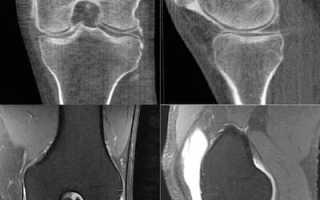

- Исследование коленного сустава

В этом случае выполняется рентген, который позволяет сканировать определенную область тела и получать серию послойных изображений. Анализ этих снимков помогает понять анатомические особенности коленного сустава и выявить возможные патологии его компонентов, таких как суставная сумка и мениск. Чаще всего данное исследование используется для уточнения предварительного диагноза при различных травмах колена.